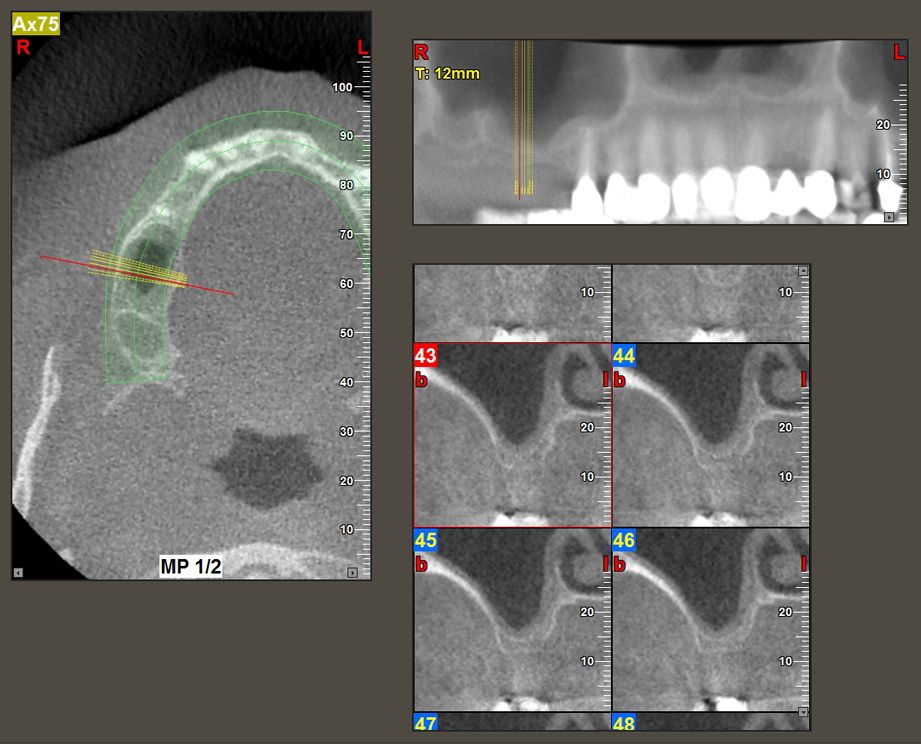

A 49-year-old female patient, a non-smoker and with nothing remarkable in her general medical history, was referred to our oral surgery practice for surgical extraction of tooth 16 and subsequent implantation. After the extraction, the patient experienced mild sinusitis trouble with the resultthat we initially waited six months before carrying out the measure. The residual bone height at the planned implant position measured 3-4 mm (Fig. 1 and 2).

Following an intermediate check (Fig. 4) a further preparation step was performed (Fig. 5). Afterwards, the hydraulic Z35P instrument was used to lift the membrane to the desired position (Fig. 6 and 7). This was followed by further piezosurgical preparation of the implant bed, concluded with a rotary bur and shoulder milling cutter up to the implant diameter of 4.8 mm. Before the implant was inserted, the augmentation material (particle size approx. 0.8-1.6 mm) was introduced underneath the Schneiderian membrane (Fig. 8).

To move the augmentation material in the direction of the maxillary sinus atraumatically, the implant was inserted very slowly by hand (Fig. 9). In the process, the membrane was pushed in the cranial direction once again. After two months, the surgical site healed without irritation. Six months later, the x-ray check showed a significant increase in opacity as an indication of ossification (Fig. 10). The prosthetic restoration was carried out with a metal-ceramic crown.